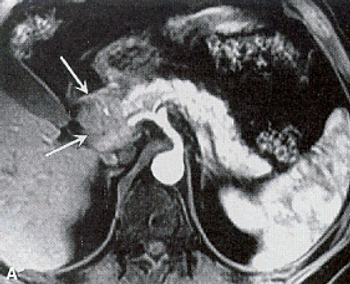

An MRI screening program for individuals at high risk for pancreatic cancer may be effective, according to the results of a short-term study.